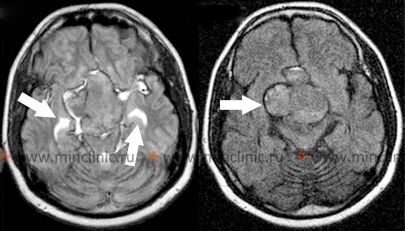

პირველად ან მეტასტაზურ თავის ტვინის სიმსივნეში უშუალოდ სისხლდენა (ინტრატუმორული სისხლჩაქცევა) ზოგჯერ შეიძლება იყოს საწყისი კლინიკური გამოვლინება, რომელიც იწვევს ინტრაცერებრული ნეოპლაზმის დიაგნოზს [1, 6]. თავის ტვინის სიმსივნეების გარკვეული ტიპები უფრო მეტად არიან მიდრეკილნი სისხლჩაქცევებისკენ, ვიდრე სხვები [6]. სისხლდენის შედარებით მაღალ რისკთან ასოცირებული ხშირი მეტასტაზური თავის ტვინის სიმსივნეები მოიცავს ქორიოკარცინომას, ავთვისებიან მელანომას, თირკმელუჯრედოვან კარცინომას და ფილტვის კიბოს გარკვეულ ტიპებს (ბრონქოგენური კარცინომა)[1, 6]. პირველად თავის ტვინის სიმსივნეებს შორის, გლიობლასტომა მულტიფორმე (ყველაზე გავრცელებული ავთვისებიანი პირველადი თავის ტვინის სიმსივნე მოზრდილებში) და, უფრო იშვიათად, მედულობლასტომა (ხშირი ავთვისებიანი თავის ტვინის სიმსივნე ბავშვებში, ტიპურად განლაგებული ნათხემში) ცნობილია, რომ ზოგჯერ ვლინდება ან უვითარდება ინტრატუმორული სისხლჩაქცევა[1, 6].

| სისხლჩაქცევა სიმსივნეში | სისხლდენა წინასწარ არსებულ მოცულობით დაზიანებაში. | პირველადი (მაგ., გლიობლასტომა) ან მეტასტაზური სიმსივნეები (მაგ., მელანომა, თირკმელუჯრედოვანი კარცინომა - RCC, ქორიოკარცინომა, ფილტვი). |